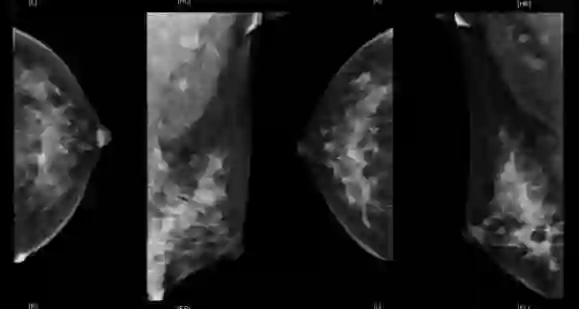

基线影像检查:乳腺MRI(2018年10月31日):左乳下象限肿块,大小6.8cm×4.8cm×6.7cm,BI-RADS:5,左腋窝多发淋巴结转移。乳腺超声(2018年11月5日):左乳肿物,BI-RADS 6;左乳下方象限可见肿物,左侧腋窝可见皮髓质结构消失淋巴结;右乳未及异常。PET-CT(2018年11月1日):左乳癌,左侧腋窝转移淋巴结可能性大。骨(-)、双肺(-)、肝(-)、脑(-)。

乳腺MRI(2018年10月31日)